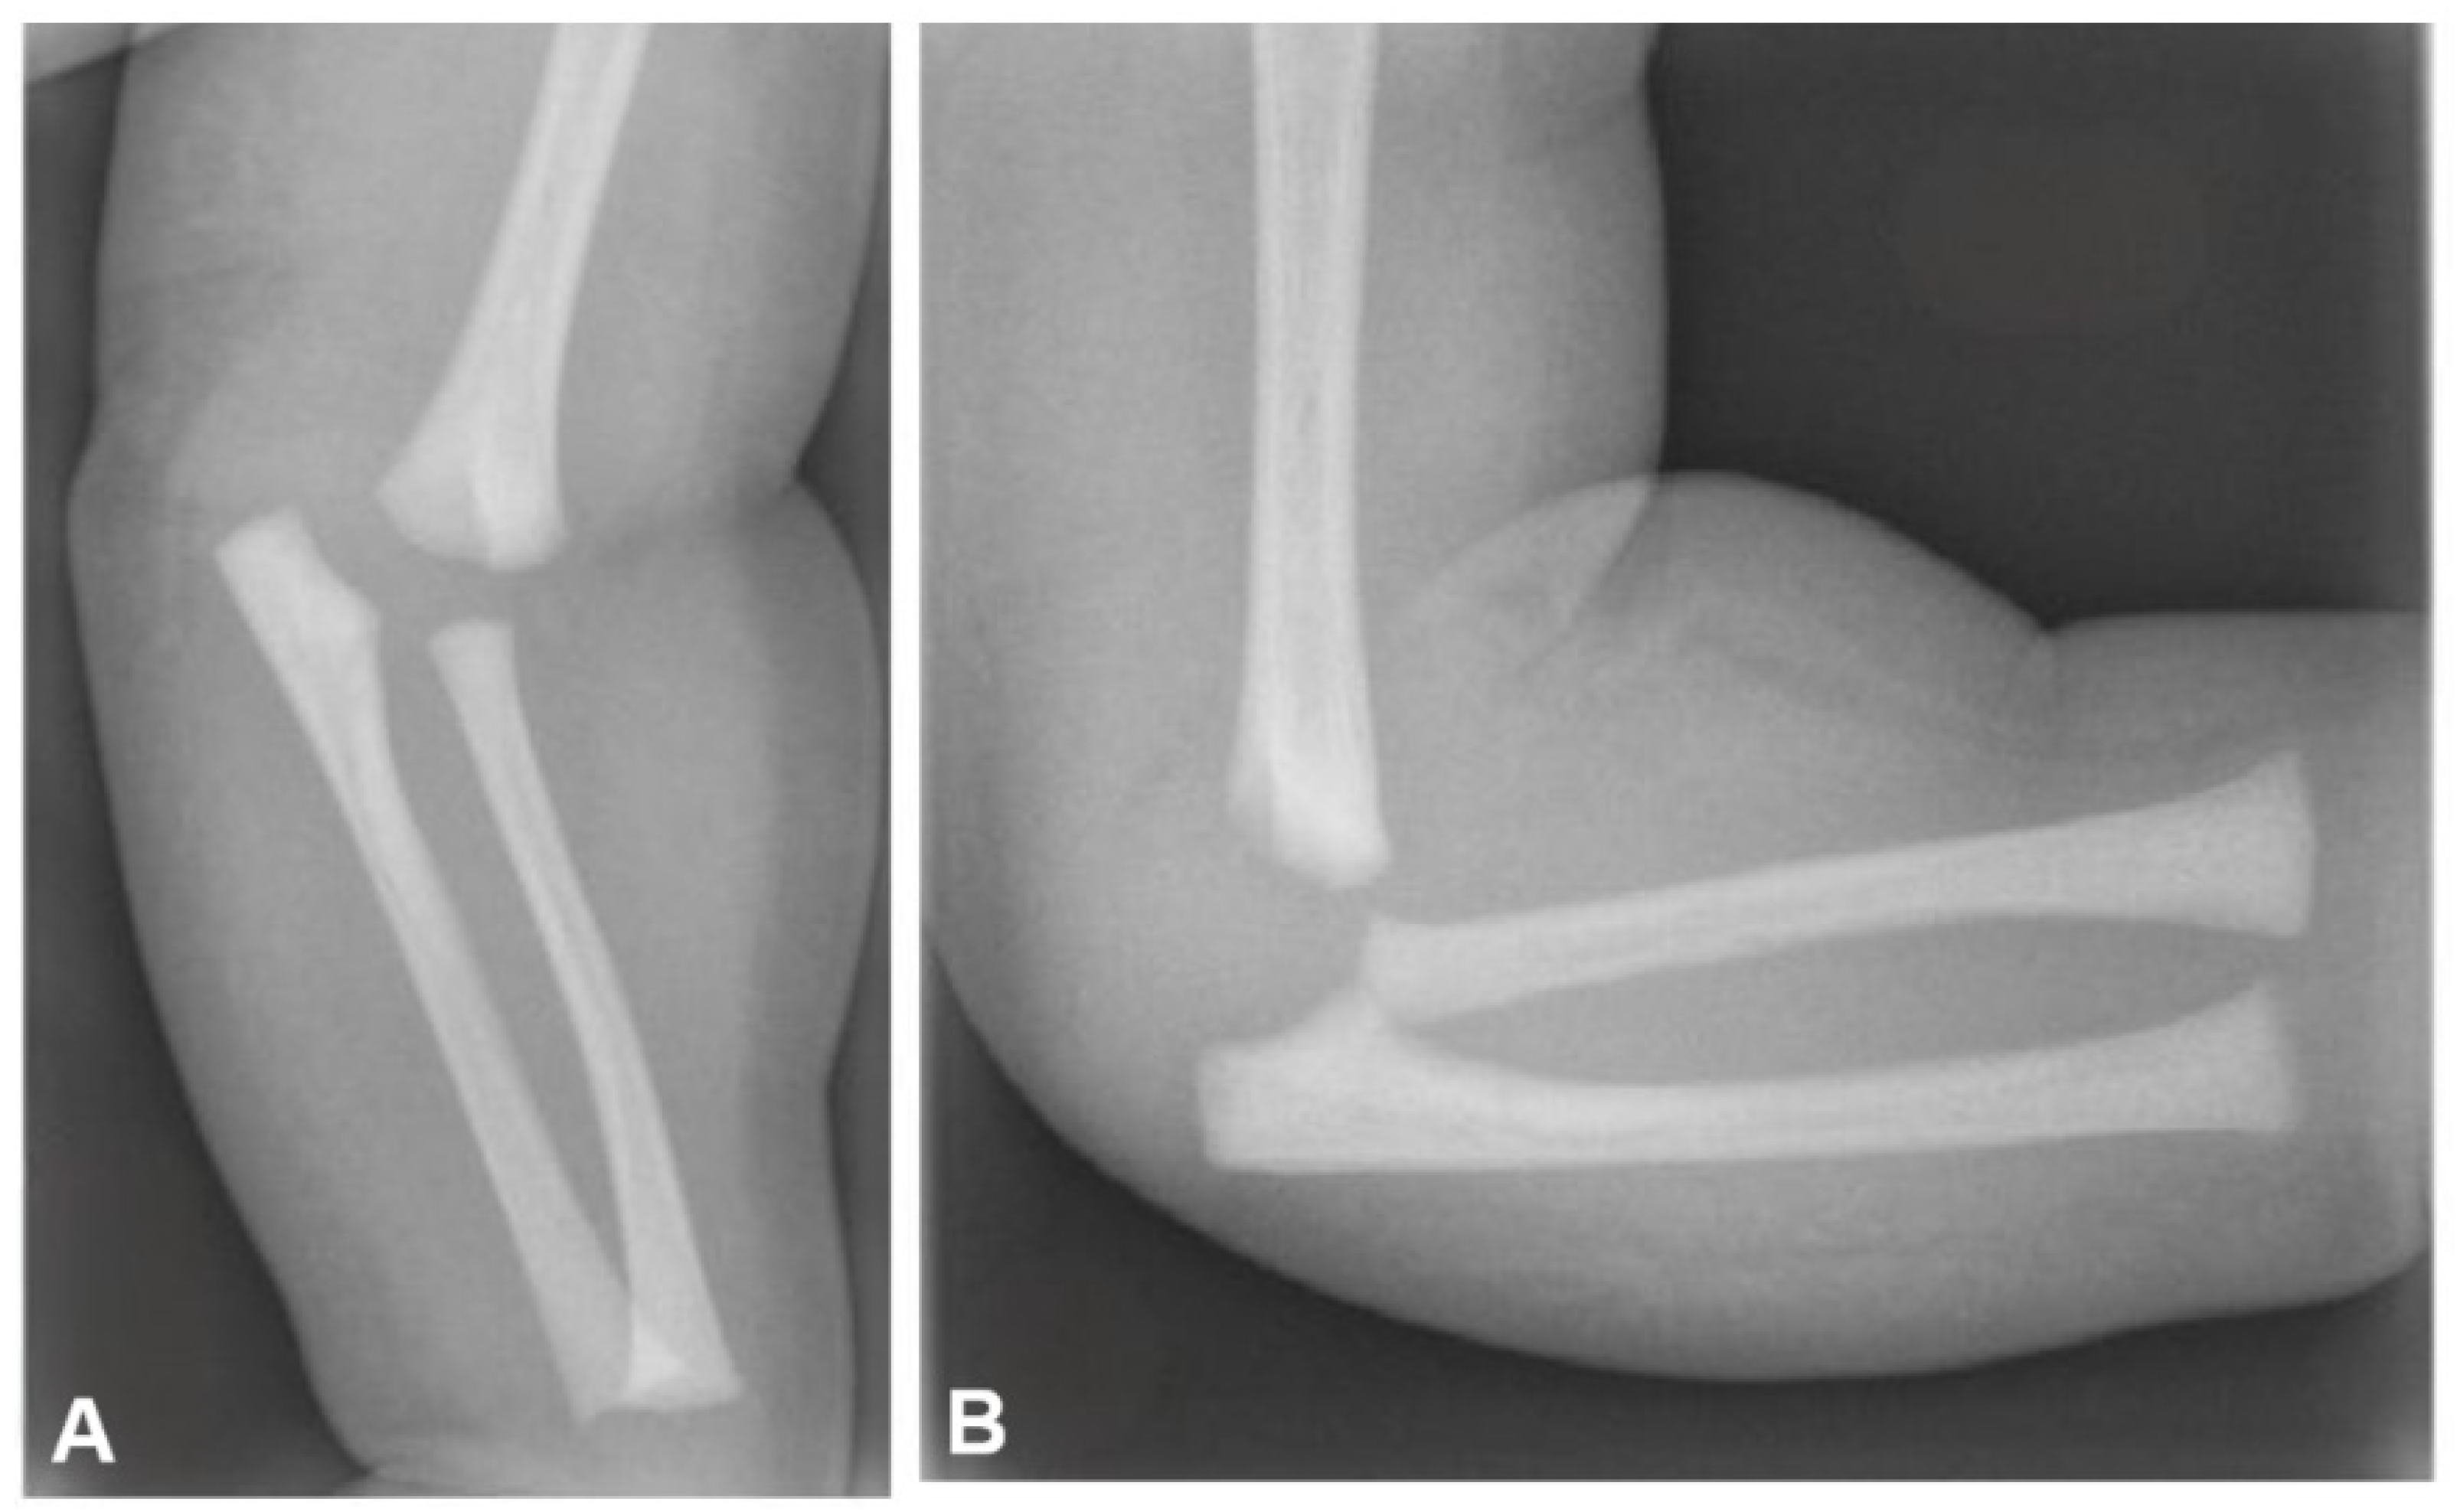

On plain radiographs, indirect signs of elbow intraarticular fractures such as joint effusion and soft tissue swelling may not always be apparent [36] (Figure 2).

Although the physeal part of DHPS may remain undisplaced in relation to the humerus, a posteromedial or medial translation of the ulna is commonly observed [32]. Interestingly, anterior displacement of the epiphysis has also been reported [42]. In newborns and infants with unossified epiphysis, ultrasonography can be a valuable diagnostic tool, especially if plain radiographs are negative or inconclusive [43]. Magnetic resonance imaging (MRI) not only confirms the diagnosis in challenging or unclear cases, particularly when the distal region of the humerus has not been still ossified, but also shows the presence and extend of concurrent injuries [30]. In the present study, we found that ultrasound and MRI examinations were utilized in 16% and 4% of cases, respectively, due to the inherent difficulty in establishing the diagnosis. We believe that ultrasonography and MRI screening should be routinely integrated in the diagnostic protocol when a high suspicion of distal humerus injury and normal elbow radiographs is apparent.